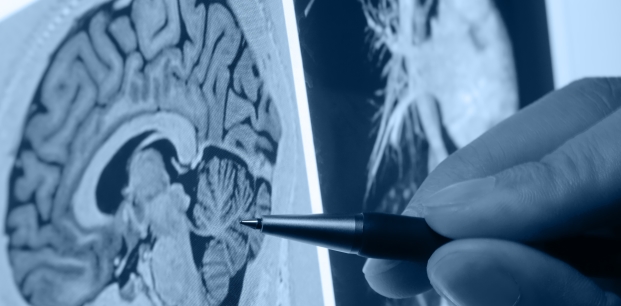

Genellikle hastanın daha önceden bilinmeyen, bir anda gelen kol, bacak tutmama, yüz, mimik hareketlerinde değişme, görmeme, duymama, yutamama gibi şikayetlerle hastaneye başvurabildiğini dile getiren Can, şu bilgileri verdi: "Bazen de inme, aniden uykudan uyanıldığında olabiliyor. Bu inmelerin saatini bilemiyoruz. Bu da önemli bir süreç. İnmede ne kadar hızlı davranırsak o kadar kar elde edebiliyoruz. Tıbbi bilgiler, makaleler inmede, 3 saate kadar damar açıldığında çok başarılı olunduğunu gösteriyor. Çalışmalarda, yeni tedavi ve gelişmelerle 12 saate kadar yapılan müdahalenin etkinliği gösteriliyor ancak ortak görüş 6 saate müdahalenin yapılabilmesi yönünde. İyi bir görüntüleme yöntemiyle beynin kanlanma alanı iyi görüntülenebilir ve iyi bir ekip koordinasyonuyla hastaya fayda sağlanabiliyor. Bizim kliniğimizde, 8 saate kadar müdahale edilip başarı sağladığımız vakalar da oldu."

İnme vakalarının 60-80 yaş arasındaki kesimde daha sık görüldüğüne dikkati çeken Can, şöyle devam etti: "İnmeye sebep olabilecek en önemli etken ailesel yük dediğimiz genetik faktörlerdir. Hipertansiyon, sigara, kolesterol yüksekliği, obezite, hareketsizlik gibi sebepler de bu soruna neden olur. Bunlar da değiştirilebilir risk faktörleri arasında yerini alıyor. Böyle bir durumla karşılaşıldığında hastanın ilk önce tomografi yapılabilecek, nöroloji doktorunun bulunduğu bir merkeze götürülmesi çok önemli. Bu iş teknik olarak nöroloji doktorlarının iyi bir muayenesinden geçiyor. Uygun hastaya, uygun dönemde müdahale edip, hastadan çok fayda sağlanabiliyor. Çünkü belli bir saatten sonra geri dönüşsüz bir yola giriliyor. Hastada uzuv kaybı, kümülatif yük çok fazla oluyor. Bu sefer de hastaya tedaviden çok zarar vermiş olunuyor. Uzun dönem hastane yatışları, hastalıklar üst üste biniyor ve tedavide geç kalmış olunuyor."

"Bu belirtilerin bir ya da birkaçının görülmesi halinde acil durum söz konusu. Erken müdahale ile olabildiğince fazla beyin dokusu kurtarılabileceğinden, kişinin en kısa zamanda tercihen tam teşekküllü bir sağlık kuruluşuna ulaştırılması gerekiyor. Eğer kişi, belirtilerin başladığı ilk 3 saat içinde hastaneye ulaştırılırsa kişiye damar açıcı tedavi (trombolitik tedavi) uygulanıyor. Kişide, ağızda eğilme, konuşma güçlüğü, tek taraflı kol ve bacakta güçsüzlük gibi belirtiler gelişmişse o anda yakınları tarafından çekilen video görüntüsü veya fotoğraf, özellikle GİA tanısının konulmasında büyük fayda sağlıyor. GİA'daki belirtiler kısa sürdüğünden, kişi acil servise ulaşana kadar düzelmiş olabiliyor.''